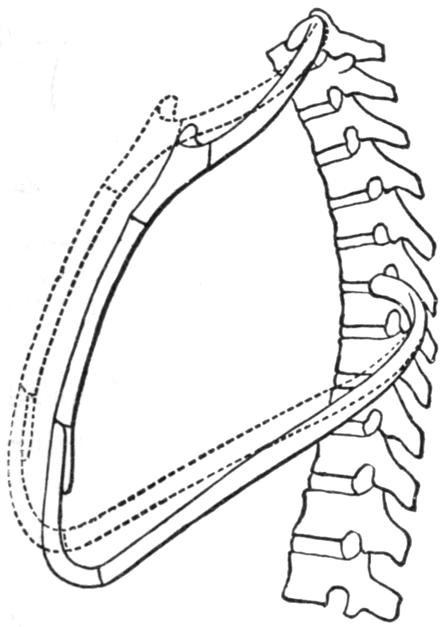

| III. | The Skeleton | H 28 |

| VI. | The Respiration | H 70 |